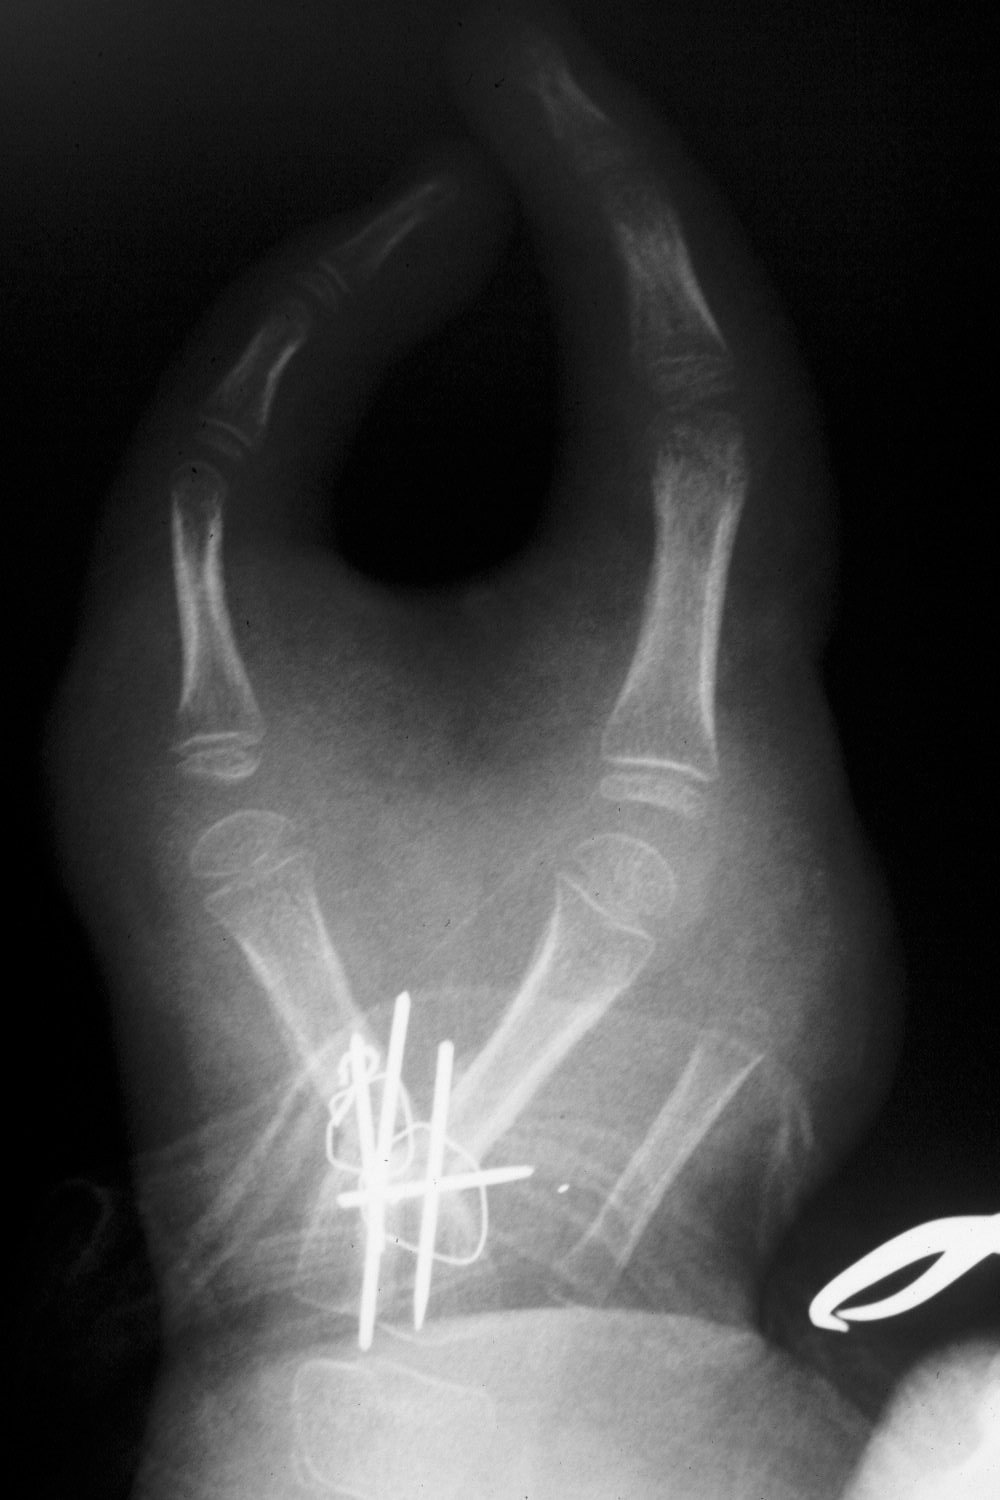

This technique allows both angulation and rotation to be changed in a single step without either bone graft or the need to discard bone. Here, the metacarpals have been simultaneously rotated and angled to separate the fingertips and in the same move position them to face each other. This created a large dorsal soft tissue defect.

Closeup of fixation: crossed K wires augmented with interosseous wires. The stretched bifurcation of the common digital artery to the adjacent sides of the digits can be seen at the distal upper end of the image behind the retractor.